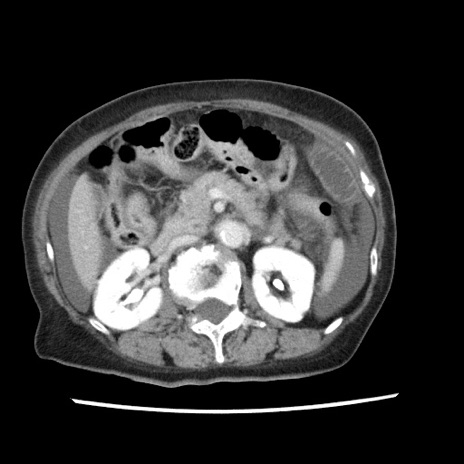

症例1(横断像)

【症例】80歳代女性

【主訴】腹痛

【現病歴】8時間前から腹痛あり来院。

【既往歴】糖尿病、脂質異常症、子宮体癌にて子宮全摘術

【身体所見】意識清明・会話良好だが腹痛で苦悶様、全腹部にわたって反跳痛と圧痛あり

【データ】WBC 13600、CRP 0.14、LDH 224、CK 90